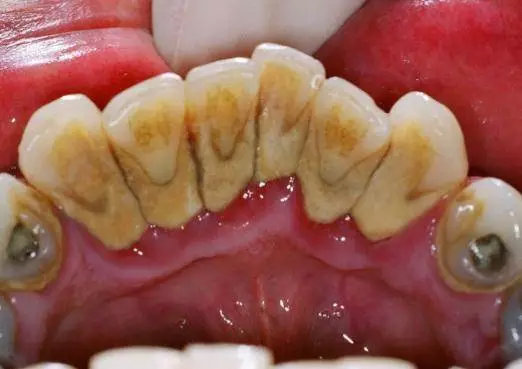

虽然每天都刷两次牙,但是外面的是干净了,但是里面却结了一层很硬的、黄黄的东西!这究竟是什么?

其实,这种黄色物质就是牙结石的初始形态,又被叫做牙垢,是沉积在牙面上已钙化的或正在钙化的菌斑及其他沉积物,一般是食物残渣、坏死脱落的口腔上皮细胞及唾液中的矿物质。

钙化是沿着牙菌斑附着牙面的内侧发生、持续进行的,刚开始形成时较软,大约数月后达到极点,就会如水壶里的水垢一样坚硬。虽然咀嚼食物、舌颊压力等原因,牙结石不会无限制地沉积,但牙结石终究不是什么好看的东西!